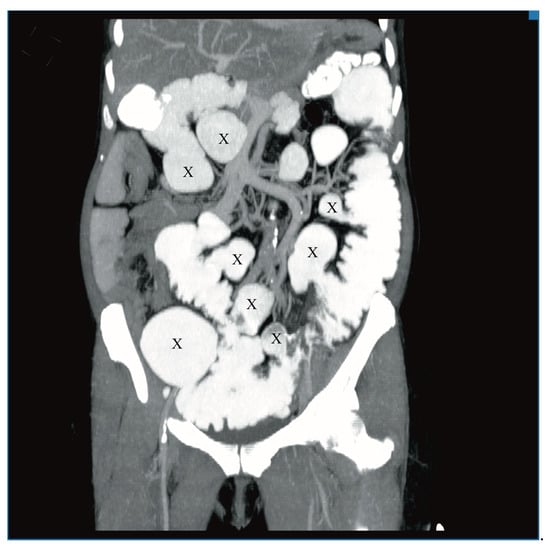

A 60-year-old woman was admitted to the emergency department complaining of acute abdominal pain, vomiting and diarrhea. Her medical history included appendectomy in childhood, hysterectomy, hepatic steatosis, chronic kidney disease (CKD) and chronic malnutrition with iron deficiency. She has also been treated for indeterminate inflammatory bowel disease (she reported taking sulfasalazine, 1.0 g three times daily) and had a twenty-year history of recurrent abdominal pain accompanied by a feeling of fullness and abdominal distension. Twenty-six years prior to admission, she underwent surgery for ileus and a large polyp in the ileum was locally resected. The patient did not provide documentation from her previous hospitalizations in other wards. Physical examination revealed absence of bowel sounds and generalized abdominal tenderness. Laboratory tests showed mild anemia and low serum protein level. Abdominal CT scan demonstrated small bowel distension (Figure 1) with ileo-ileal intussusception caused by one of multiple pedunculated lipomatous polyps arising from the mesenteric border of the jejunum (Figure 1 and Figure 2). Multiple giant diverticula were also visualized (Figure 1 and Figure 3).

Figure 1.

Contrast-enhanced computed tomography (CT) image of the abdomen, axial section. Multiple jejunal lipomas (white arrows), distended jejunum (triangles), one of the diverticula (X) and intussuscepted jejunum with a lipoma as the leading point (black arrow).